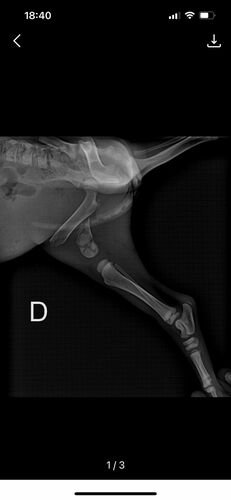

Ela e a irmã foram abandonadas na rua e um carro atropelou apenas ela, onde teve fratura total no fêmur.

(segue imagens do raio x)